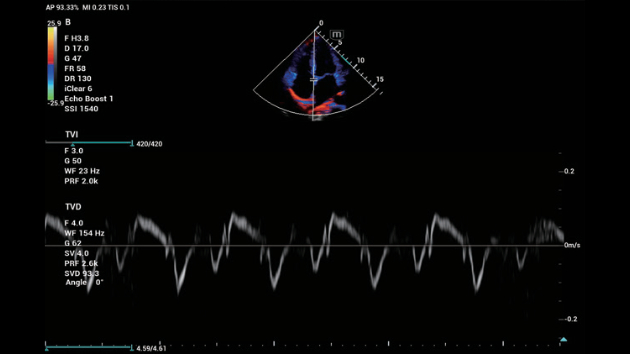

ZST+ ??? ???? ?? ???

ZST+ ???? ???? ??? ???? ??? ?????. ??? ???? ?? ? ???? ?? ??? ?? ??? ?????. ??? ??? ? ?? ??? ??? ???? ?????? ??? ???? ???? ??? ?? ?? ?? ?? ???? ?? ??? ?? ??? ?????.